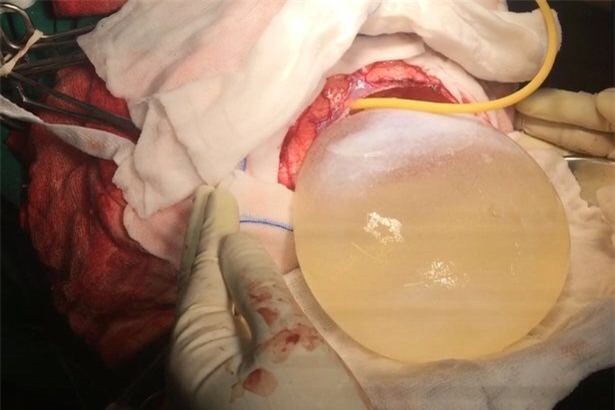

Nang sán này nặng 675g và có kích thước 12,2x11x9,8 cm. "Tôi cho rằng bọc nang này đã phát triển trong đầu cô bé cách đây 8-10 năm. Càng phình to ra, nó càng gây ảnh hưởng nhiều và khiến cơn đau đầu ngày càng dữ dội”, bác sĩ nói.

“Nang sán này to bằng một nửa kích thước bộ não, trông như một quả bóng căng phồng và rất nguy hiểm bởi nó có thể vỡ bất cứ lúc nào, khiến cô bé tử vong ngay lập tức”. Bác sĩ Solanki nói gia đình cô bé rất sốc khi biết con gái mình mang một ổ nang sán lớn đến như vậy.

Quá trình phẫu thuật trong 2 giờ 30 phút, bác sĩ Solanki và các cộng sự đã bóc tách thành công ổ nang mà cô bé không gặp phải bất kỳ biến chứng nào.